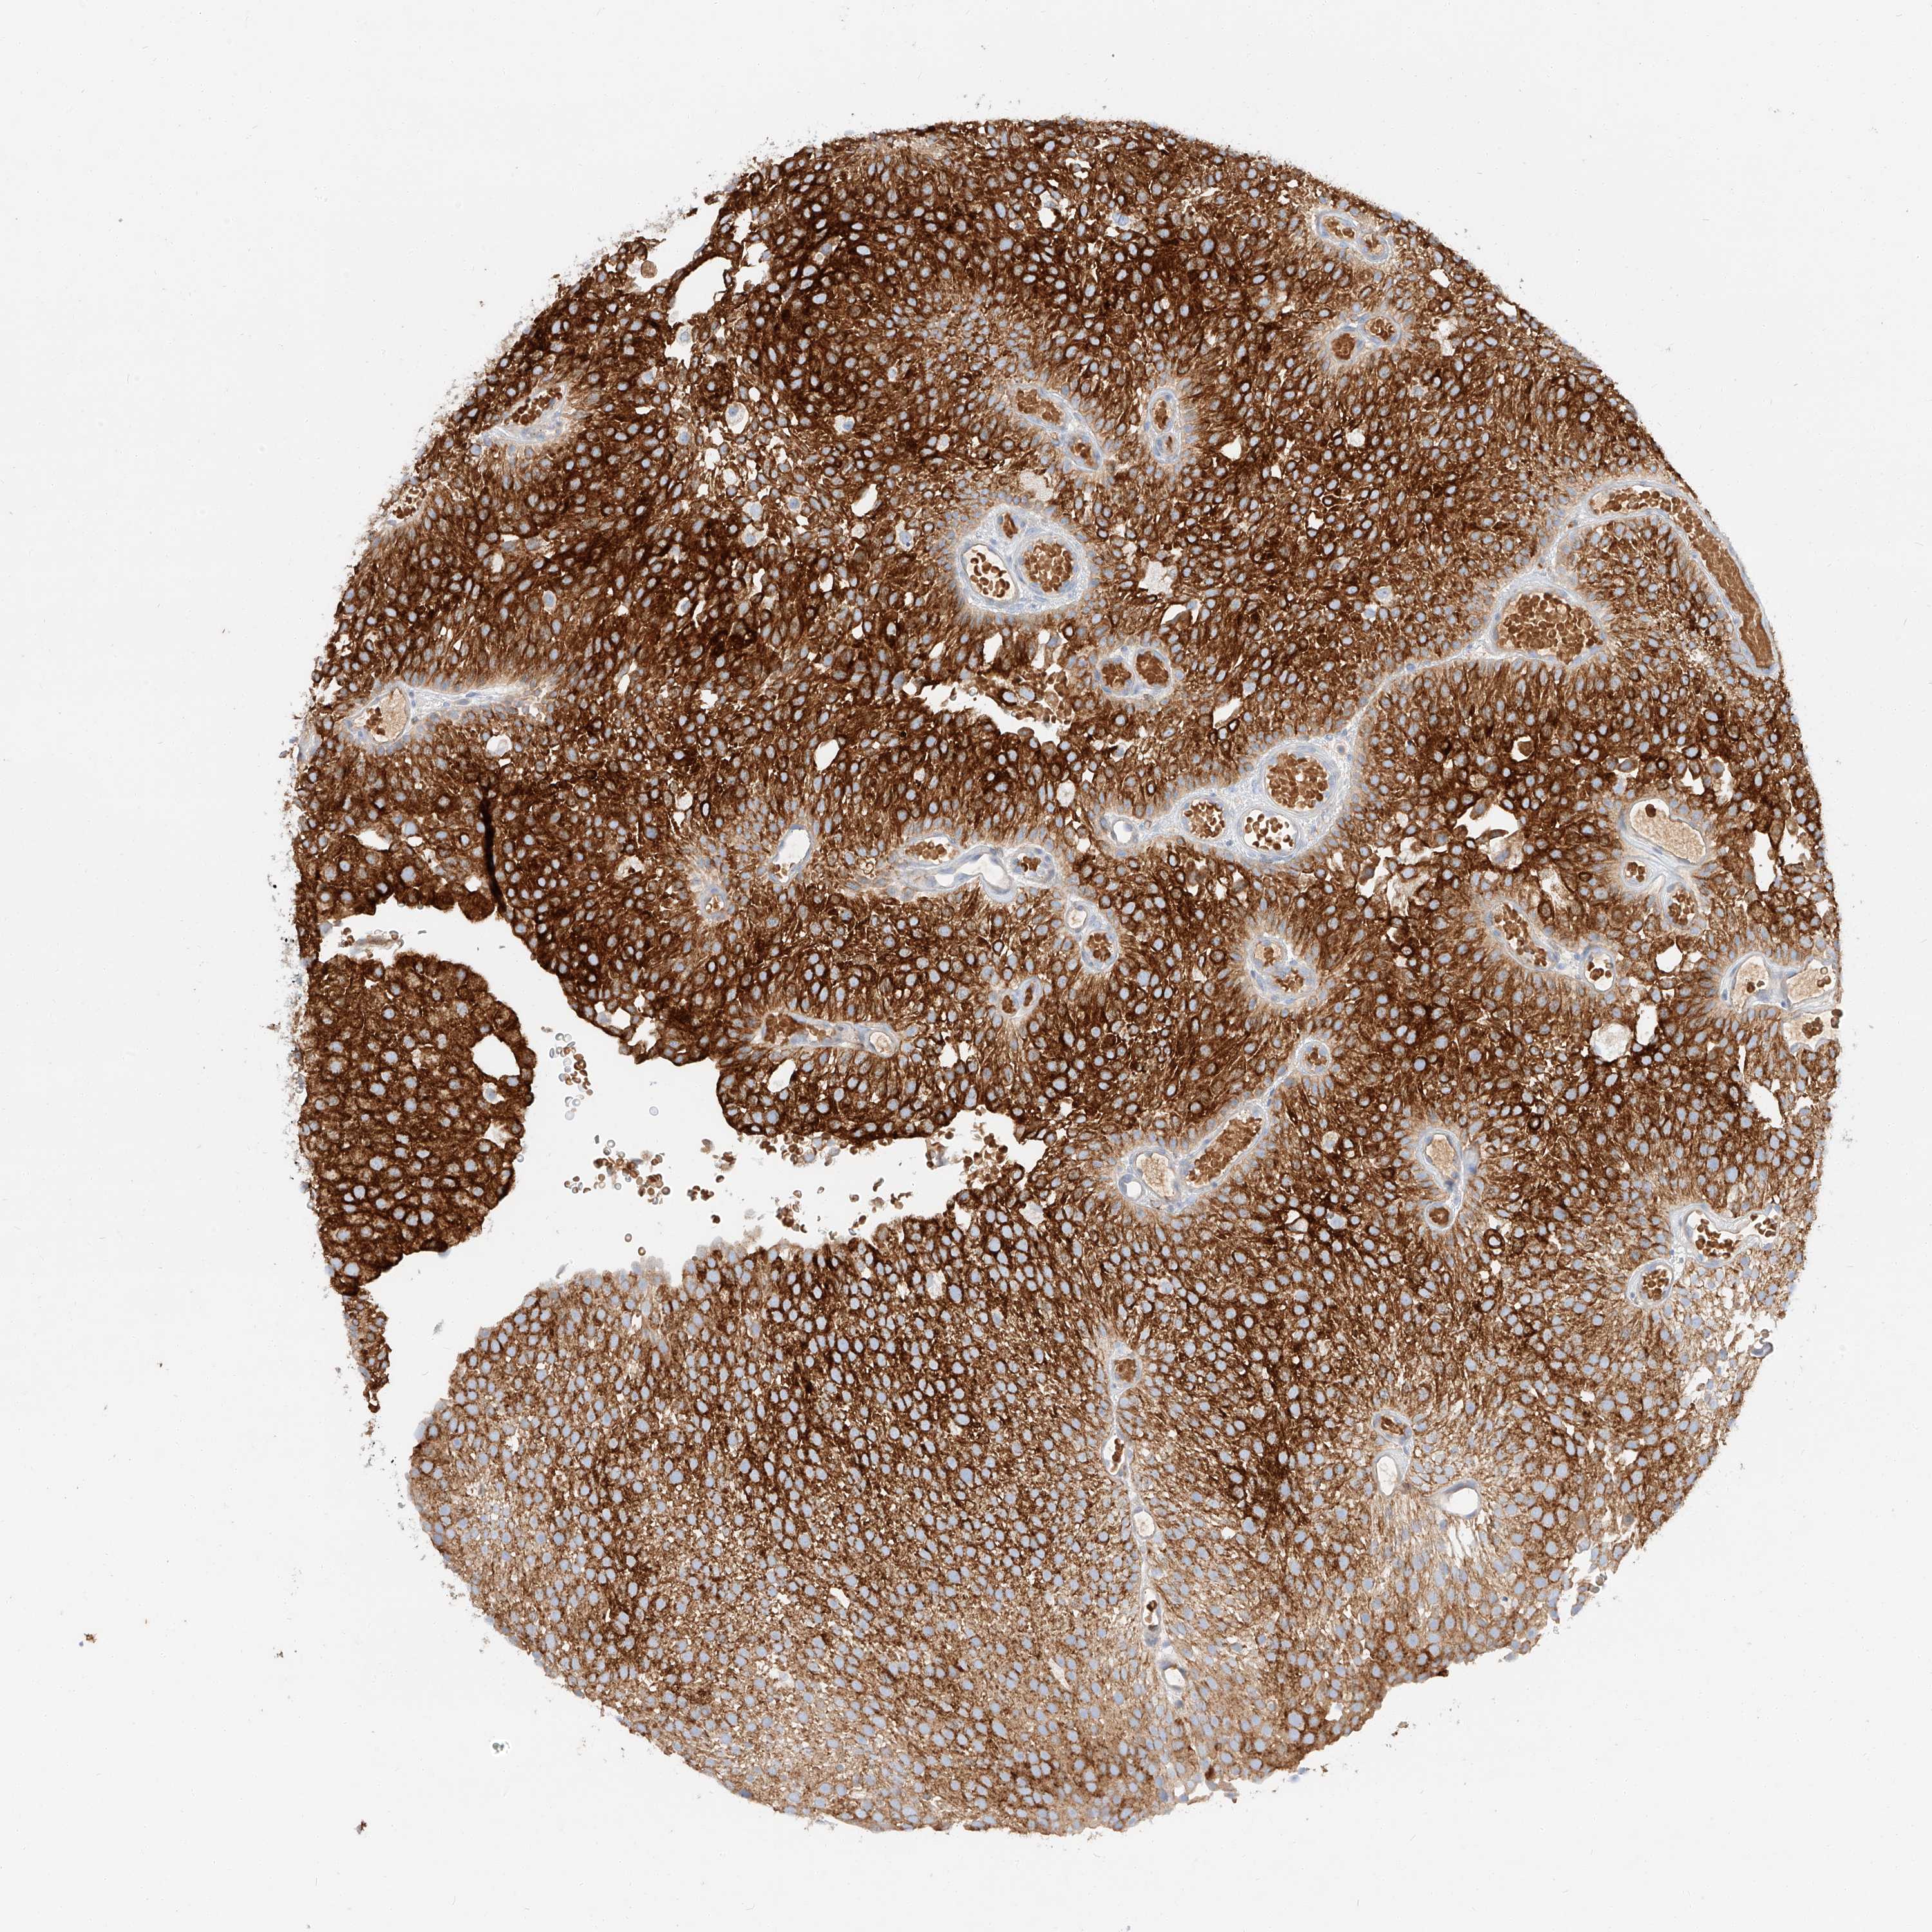

UROTHELIAL CANCER - Protein expressioni

A mouse-over function shows sample information and annotation data. Click on an image to view it in a full screen mode. Samples can be filtered based on level of antibody staining by selecting one or several of the following categories: high, medium, low and not detected. The assay and annotation is described here.

Note that samples used for immunohistochemistry by the Human Protein Atlas do not correspond to samples in the TCGA dataset.

Antibody stainingi

Antibody staining in the annotated cell types in the current human tissue is reported as not detected, low, medium, or high, based on conventional immunohistochemistry profiling in selected tissues. This score is based on the combination of the staining intensity and fraction of stained cells.

Each image is clickable and will lead to virtual microscopy that enables deeper exploration of all samples and also displays staining intensity scores, fraction scores and subcellular localization as well as patient and tissue information for each sample.

Antibody HPA029712

Antibody HPA029713

Staining

High

Medium

Low

Not detected

Intensity

Strong

Moderate

Weak

Negative

Quantity

>75%

75%-25%

<25%

None

Location

Nuclear

Cytoplasmic/membranous

Cytoplasmic/membranous,nuclear

Urothelial carcinoma, Low grade

Urothelial carcinoma, High grade